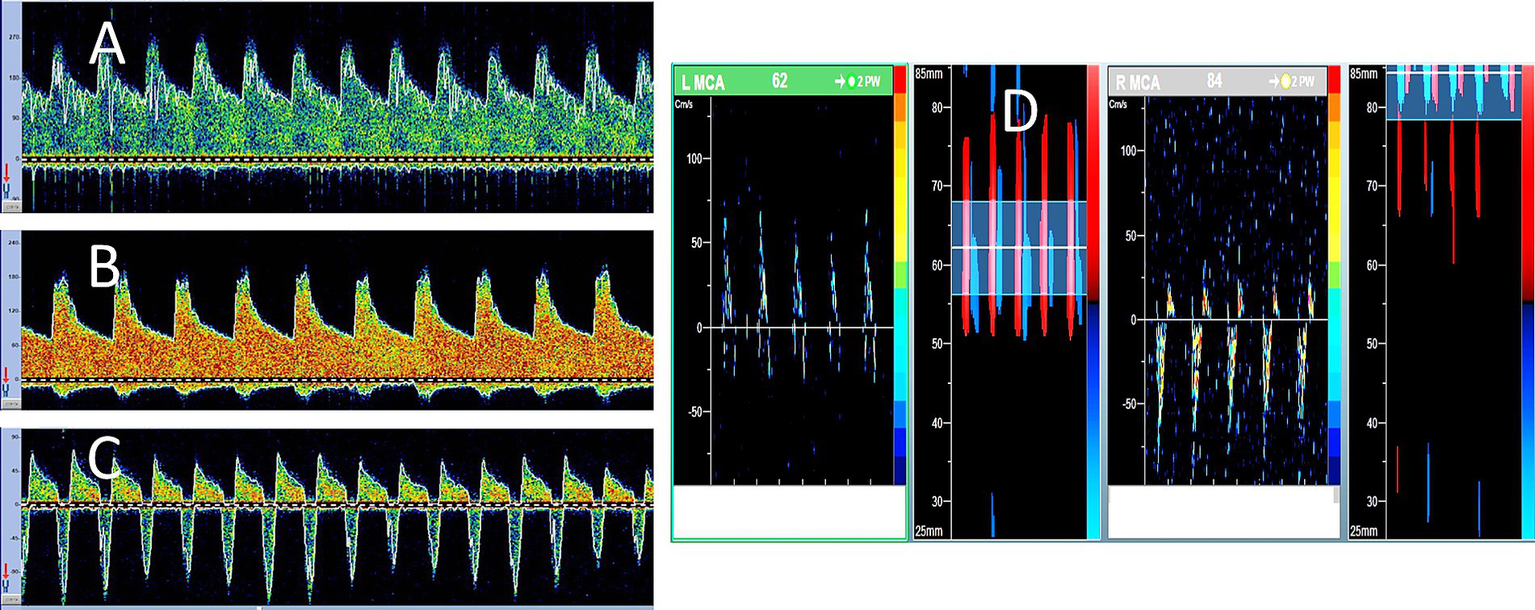

Figure 2

Serial transcranial Doppler (TCD) findings in brain death. A 48-year-old woman was admitted with severe subarachnoid hemorrhage due to an anterior communicating artery aneurysm rupture. She underwent urgent clipping and was monitored regularly with TCD. Her level of consciousness remained poor, while ICP continued to increase despite all therapeutic measures. During the 7 days of follow-up, his TCD spectra showed serial evolution from a normal-looking waveform (A) on day 2 to a higher resistance waveform (B) on day 4 to the oscillating pattern (suggestive of cerebral circulatory arrest) on day 5 (C). No brainstem reflexes were observed, and TCD spectra showed further evolution of the oscillating Doppler spectra in both middle cerebral arteries (D).